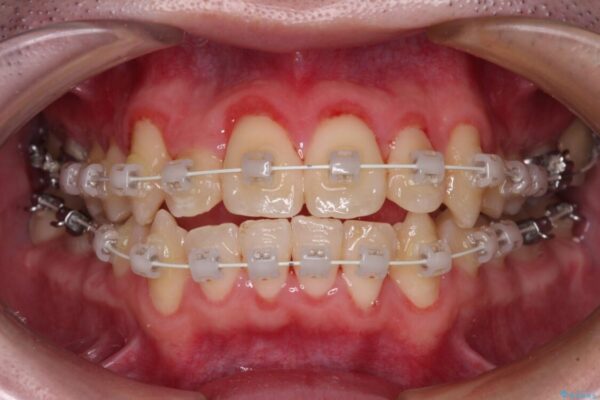

治療途中

• 全顎的なクロスバイト 補助装置を用いてワイヤー矯正 治療途中画像

シザーズバイト改善のために補助装置を使用しながら、ワイヤー装置にて全体の歯列を整えることとしました。

シザーズバイトは強く咬合する奥歯を移動させるため、多くの場合においてワイヤー矯正の装置のみでは改善が困難となります。

奥歯の咬み合わせ改善は治療初期からしっかりとアプローチする必要があるため、補助装置を積極的に利用します。